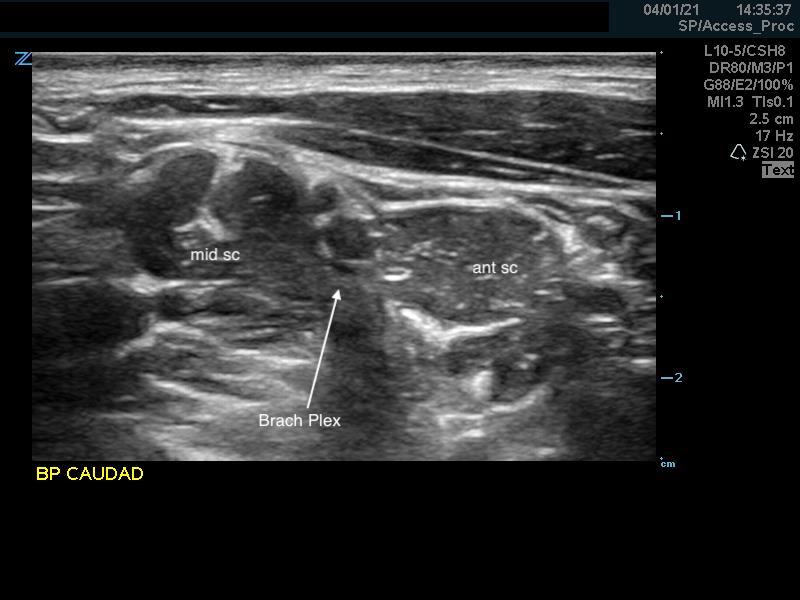

- Identify the middle scalene muscle posterior to the anterior scalene muscle.

- The interscalene space is between these 2 scalene muscles and contains the brachial plexus

- Visualize the brachial plexus here as a stack of circles with hypoechoic centers

- The plexus will look more echogenic, bundled and honeycombed in the caudal interscalene space

- Alternative Pre-scan – Backtracking from the Supraclavicular Space

- Identify the brachial plexus in the supraclavicular fossa as in the supraclavicular brachial plexus block

- The subclavian artery is the main landmark at this site.

- The brachial plexus is seen immediately adjacent to the superior-posterior border of the subclavian artery as a grouping of small hyperechoic circles with hypoechoic centers, similar to a cluster of grapes.

- Backtrack from this site to the interscalene space by sliding the probe cephalad while keeping the plexus in the center of the image.

- The plexus will change conformation and become more hypoechoic as you slide superiorly.